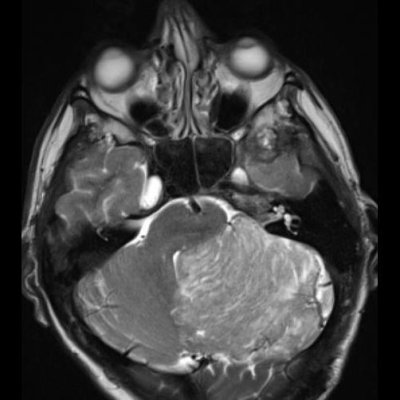

24 yaş, E

Baş ağrısı

Lhermitte duclos

Lhermitte-Duclos hastalığı (Dysplastic cerebellar gangliocytoma)

Dysplastic cerebellar gangliocytoma(Lhermitte-Duclos hastalığı)

Lhermitte-Duclos hastalığı

Displastik serebellar gangliositoma